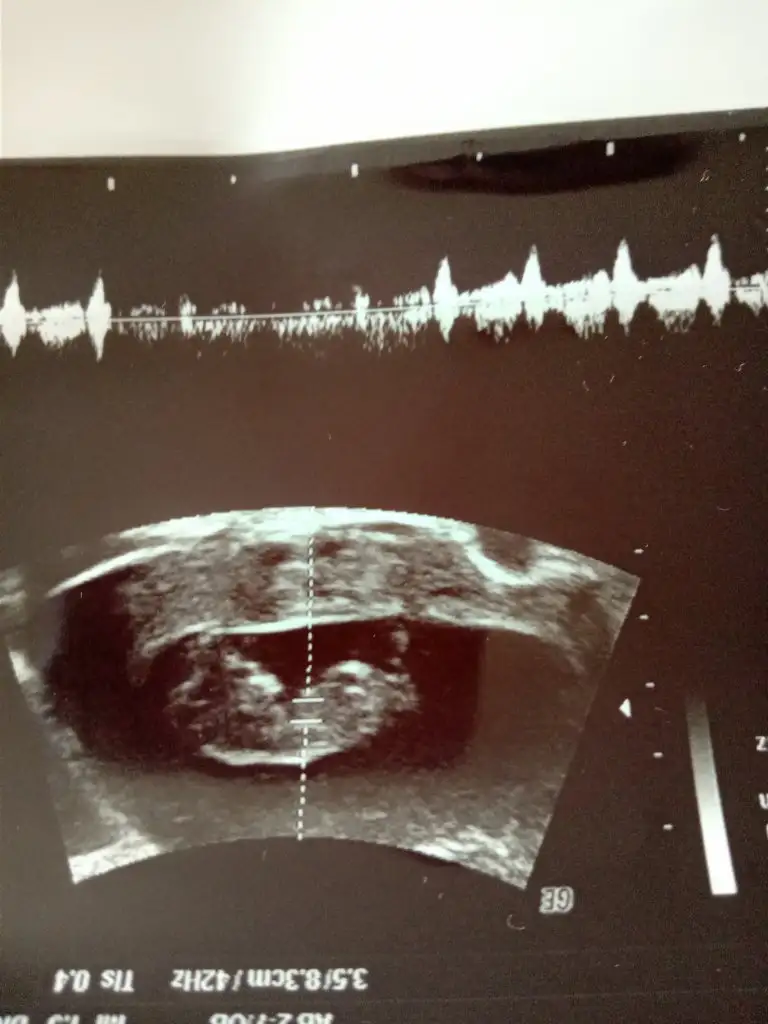

Teşekkür ederim ben sizin sandım herkes siiz etiketleyinceRc ederim diger taraf benim konum degil ama orası aktifde değil arada etiket yapanlar var onlara cvp veriyorumbuna göre kız ama tutmayabilir kese konumu en iyi nub 11 12 13 haftalar olmalı

Sizinki kıza benziyorHer iki doktor farkli soyledi cinsiyetini 10ngun sonra kesin soyleriz dedi son fotograflar yeni bacak arasi net dikattli bakinca belki fikrin netlesir belki canim![]()

Sizinki de erkek bebek gibi14 haftalık tahmin edermisiniz

kıza benzettimMerhabalar bizde burda 11 haftadaydik bizede tahmin edebilirmisiniz rica etsem ❤

Teşekkür ederim önce sağlık tabiki ama gönlüm den de kız geçiyorkıza benzettim